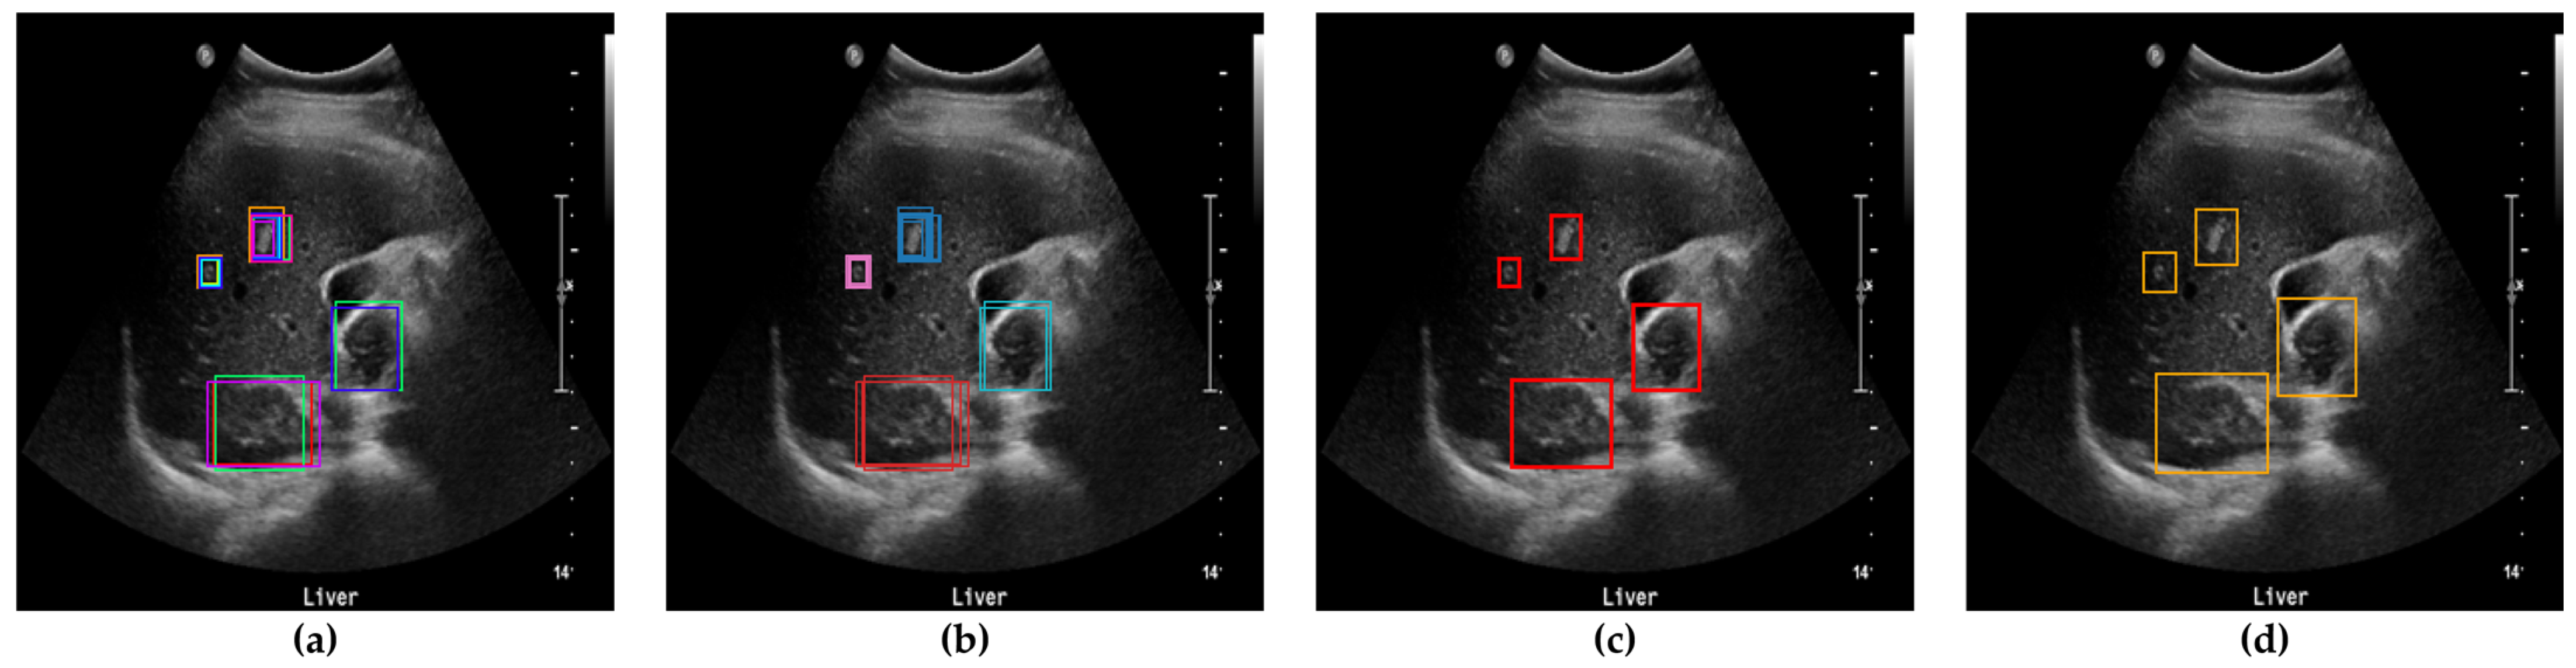

3.3. Performance of Lesion Classification

The lesions identified through SM-WBF were classified using a CNN. Among various models, we selected EfficientNet-b0, known for its efficiency and performance, for comparison. As shown in Figure 8, the lesions were classified into three classes: benign, malignant, and error. For training, the image size was resized to 300 × 300, and the input size of EfficientNet-b0 was modified from its default 224 × 224 to 300 × 300. This adjustment was made to ensure accurate classification, as reducing the image size excessively could compromise the model’s performance.

If multiple boxes were detected in a single image, all boxes were classified. Boxes classified as error were ignored, and the output was determined as benign if only benign boxes were present. However, if even one box was classified as malignant, the output was set to malignant. Due to the nature of medical screening, where high sensitivity is more clinically significant than specificity, this approach was adopted to maximize practical utility for end users. Additionally, a 5-pixel padding was applied to enhance the visibility of lesion contours and facilitate comparisons between the internal color of the lesion and the surrounding liver tissue.

As shown in Table 2, the difference with and without padding was substantial. Without padding, the lesion contours resulting from clustering could become ambiguous, and comparing the color of the surrounding liver tissue with the lesion itself becomes nearly impossible. When padding was applied, these comparisons were feasible, leading to improved results. The detailed reasons for this will be discussed further in the discussion section.

Figure 8. The lesions were classified into three classes using EfficientNet-b0.